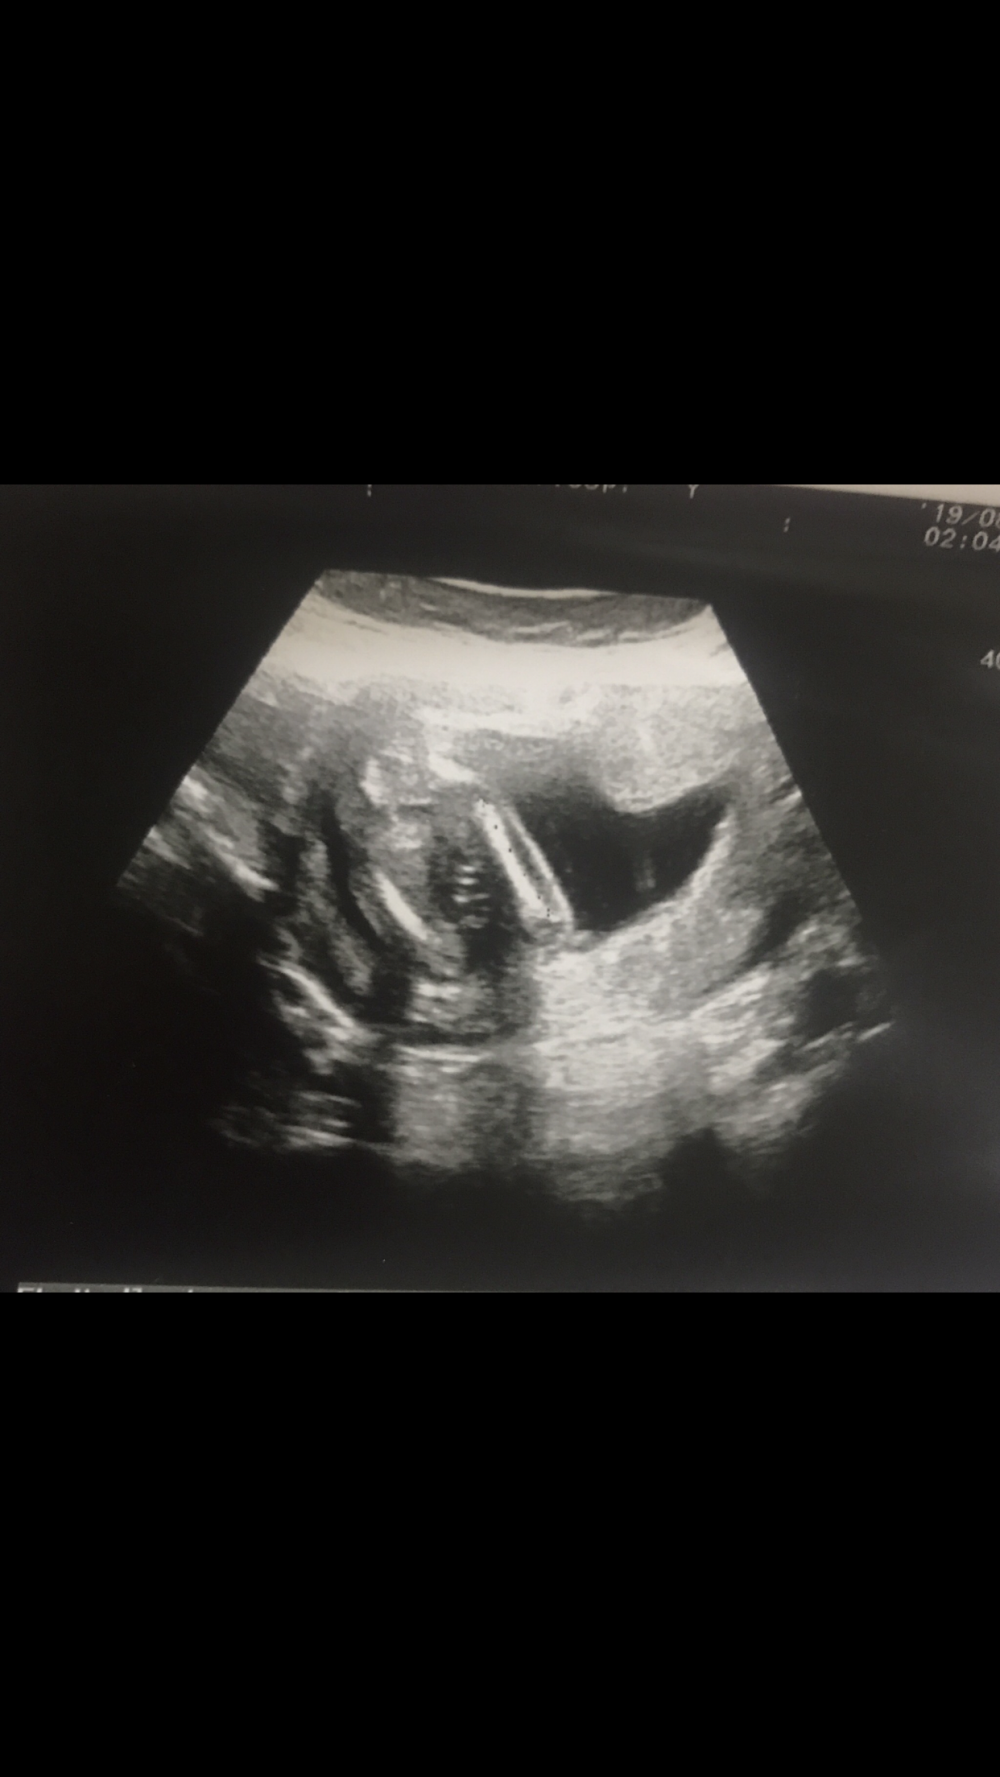

كيفكم يابنات رحت اليوم عند دكتوره اول مره اروح لها وسوت أشعه واخذت القياسات وسمعتني النبض وهي تاخذ قياس الفخذ قالت لي ده عظم الفخذ حقها 🥰💜💜💜 الحمدلله حمداً كثيراً قلت لها يعني بنت قالت ممكن 💜 ليتها اكدت لي اعتبر الحين بنص الرابع المفروض يكون باينكيفكم يابنات رحت اليوم عند دكتوره اول مره اروح لها وسوت أشعه واخذت القياسات وسمعتني النبض وهي...

وسوت أشعه واخذت القياسات وسمعتني النبض وهي تاخذ قياس الفخذ قالت لي ده عظم الفخذ حقها 🥰💜💜💜

الحمدلله حمداً كثيراً

قلت لها يعني بنت قالت ممكن 💜

ليتها اكدت لي اعتبر الحين بنص الرابع المفروض يكون باين